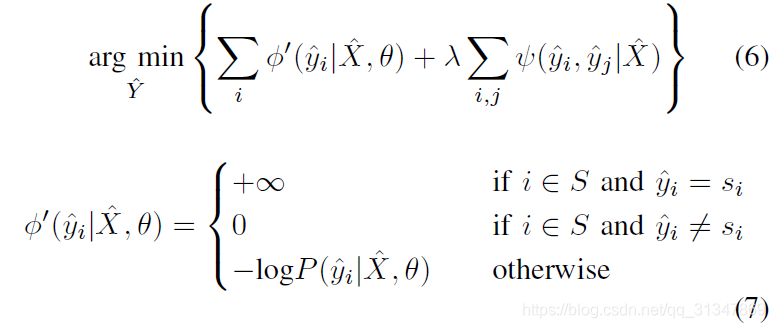

为方便实现,将等式(5)转换为无约束优化等式:

(2)network update step

对 CNN 网络参数进行单独优化:将

Y

^

\hat Y

Y^ 固定,此时优化目标(1)简化为:

将等式(8)也转换成无约束的优化等式:

但是这还不是最终的目标函数,作者还根据像素的重要程度进行了改进。

3. Weighted Loss Function during Network Update Step

在 CNN 网络的更新阶段,会根据当前的分割结果 Y ^ \hat Y Y^ 进行 fine-tuning。作者提出的 fine-tuning 不是对所有像素都进行处理,而是根据各像素的 confidence 对它们进行处理(对比之前有的方法是对所有像素都进行处理)。

比如说,用户提供的 scribbles 相比其他像素要具有更高的 confidence,所以就对 loss function 有更大的影响,因此对公式(3)即一元项进行加权:

权重为

w

(

i

)

w(i)

w(i),其函数定义表示了若像素

i

i

i 属于用户提供的 Scribble,则其权重为

w

w

w,否则权重为 1。

对公式(9)进行加权得到:

--------最终我们需要优化的目标函数就是 (10) , (12)---------